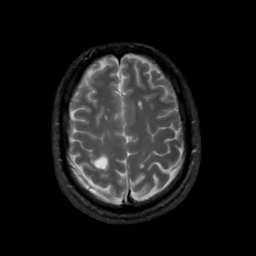

MR Study #3, February 24, 1991 -- Slice #39

[Home][Help][Clinical][Tour 1][Tour 2] Slice 39